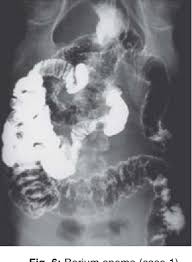

A And B Peutz Jeghers Syndrome In 22 Year Old Woman Contrast Study Download Scientific Diagram